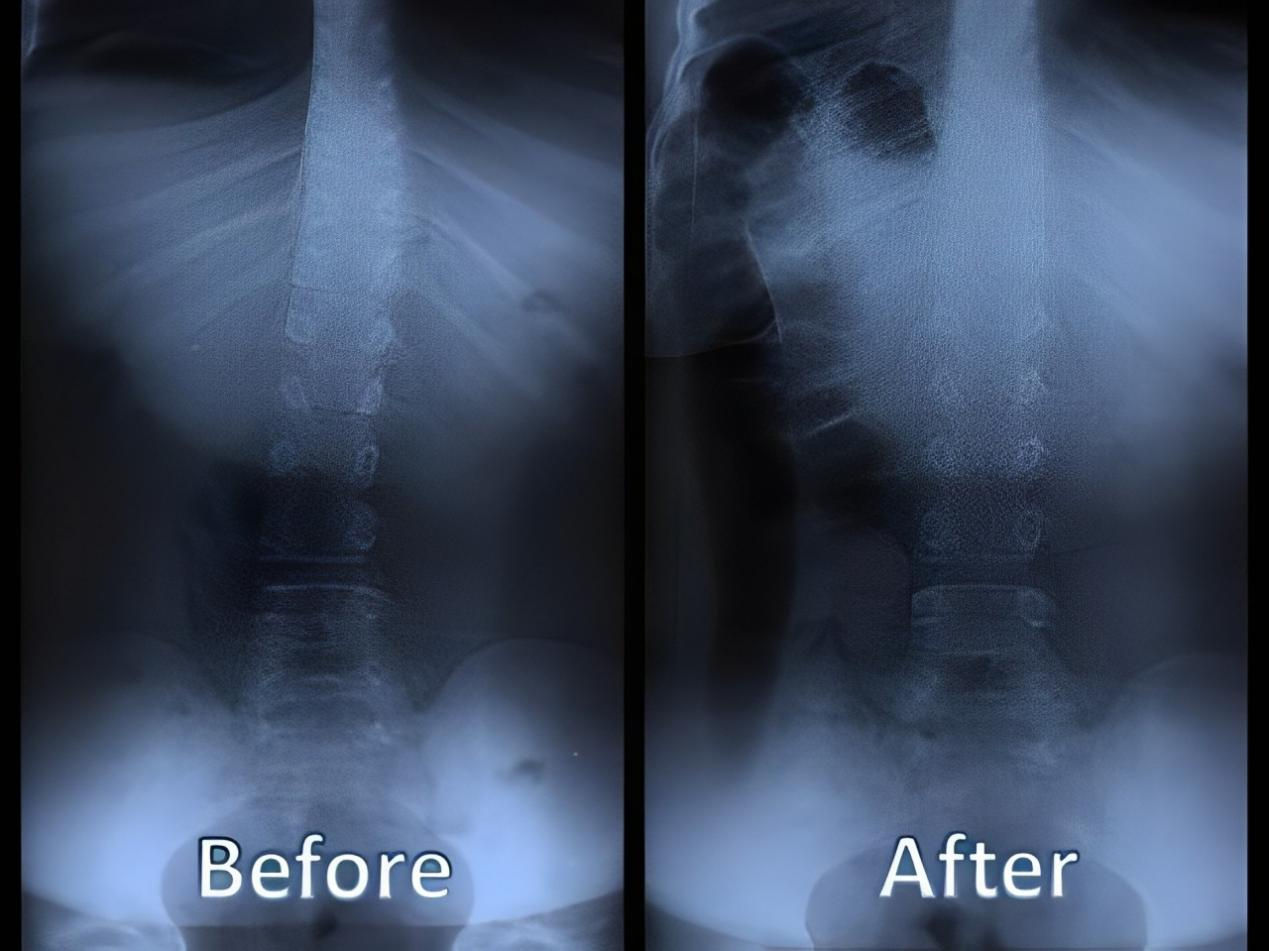

四、 恢復脊椎自然曲度

五、矯正完和矯正后的對比案例: